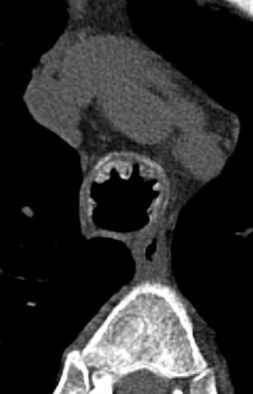

Tracheobronchopathia osteochondroplastica

trachéobronchopathie ostéochondroplastique (TOCP)

- Calcifications et epaississements nodulaires

- Trachée distale et bronches souches proximales

- Epargne la zone postérieure

Tracheobronchopathia Osteochondroplastica